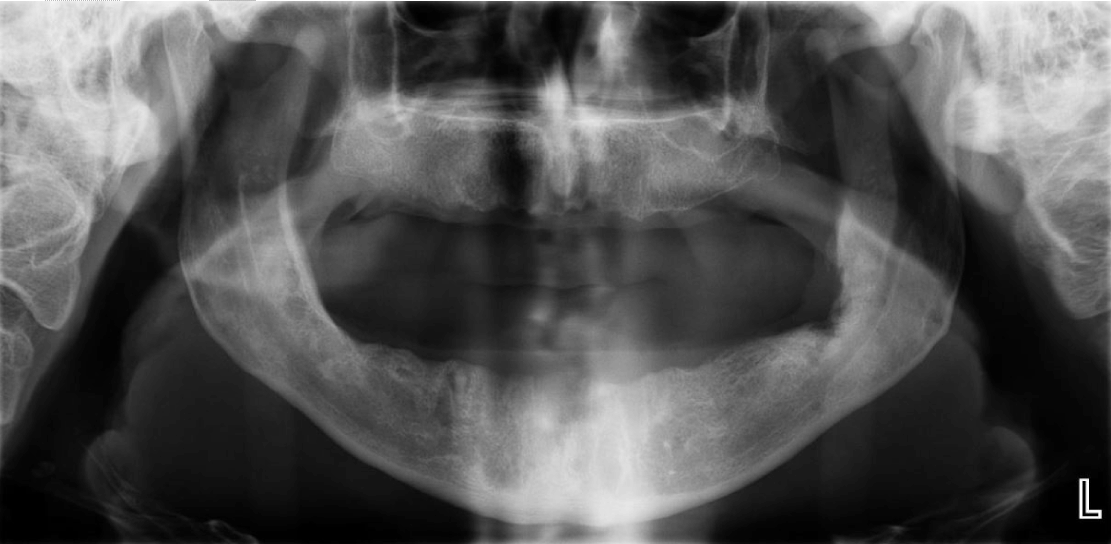

A 54-year-old edentulous man was referred to our outpatient department, complaining of a pain in the deep lingual aspect of the mandible on his left side, when he was wearing his lower denture. His past medical history was free and his surgical history only comprised of an appendicectomy. A bulge that was thought to be arising lingually of the left inferior 3rd molar post-extraction socket, right under the internal oblique line, was palpated upon clinical examination and the patient was scheduled for surgical removal of the diagnosed exostosis in order to relieve his relentless pain. Before proceeding in the operation, the patient was radiographically assessed, but nothing unusual was noticed (Figure 1). In the operating room, we performed left inferior alveolar nerve block along with several lingual and parietal local infusions. Then we went on with a longitudinal incision on the edentulous alveolar ridge of the left mandible and we raised the mucoalveolar flap. This revealed an absolutely normal bone surface and at the same time an abnormal mass within the corresponding soft tissues. Initially, it was thought to be a residual root of the 3rd molar (Figure 2), which was extracted several years before. This was a two step procedure for an initial unsuccessful attempt from a dentist was followed by an oral surgeon’s intervention. Then as we tried to pull out the foreign object, we surprisingly discovered that it was a suction tip (Figure 3). After removing it, the wound was closed with continuous locked suture (Figure 4). The patient was prescribed antibiotics and analgesics and was discharged.

Figure 1: Orthopantomogram showing left 3rd molar post extraction socket.